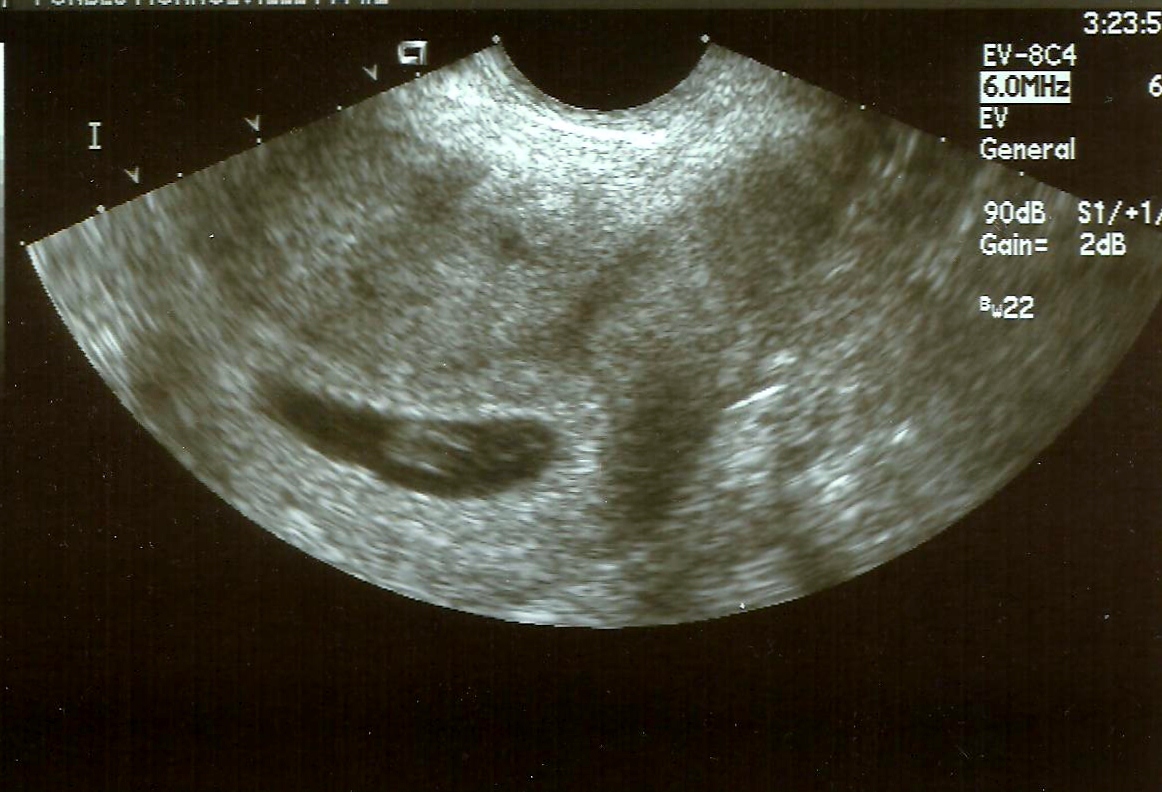

Bean- 7 weeks, 3 days

They brought me back to the ultrasound room 20 minutes after my scheduled time.  On edge and anxious, the ultrasound tech inserted the wand and I took a deep breath, squeezing my husband's hand.  In just a few moments, we would know.  We would know if our baby had made it through my scary week.  Within a few seconds, I heard her speak magical words to us, "I see the heartbeat and boy, is it going!".  She turned the screen towards us and there in the middle of that hazy, white mass was a wildly flickering spot- our baby's heart beating.  I laughed, then I cried and then I breathed a huge sigh of relief.  She did a count on the baby's heart rate- an amazing 175 beats per minute!  Bean had went from a heart rate of 105 one week before to 175!  Wow....  She did all the necessary measurements and then gave us our first official due date- February 14, 2012. <3  Happy Valentine's Day to us... :)

My anxiety has greatly subsided since this ultrasound.  We had reached one incredible milestone- a baby with a strong heartbeat past 7 weeks.  Today we reached another- I have made it to 8 weeks of pregnancy.  I haven't made it to the 8th week in pregnancy since I was pregnant with my son 13 years ago.  Tomorrow we will hopefully reach another- making it to our first prenatal appointment with our OB/GYN.  My hope is returning, my faith in my body is being restored...  I know I am not completely out of the woods.  You never are until you are actually holding that tiny baby in your arms after 9 months of pregnancy, and hours of labor and pushing.  But I have hope.  My hope is looking at you in that picture above.